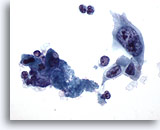

Figure 84

Bronchial wash

Lower magnification showing squamous cell carcinoma in the upper left portion of the field. 20x

Bronchial wash

Lower magnification showing squamous cell carcinoma in the upper left portion of the field. 20x

Figure 84

Bronchial wash

Lower magnification showing squamous cell carcinoma in the upper left portion of the field.

20x

Bronchial wash

Lower magnification showing squamous cell carcinoma in the upper left portion of the field.

20x